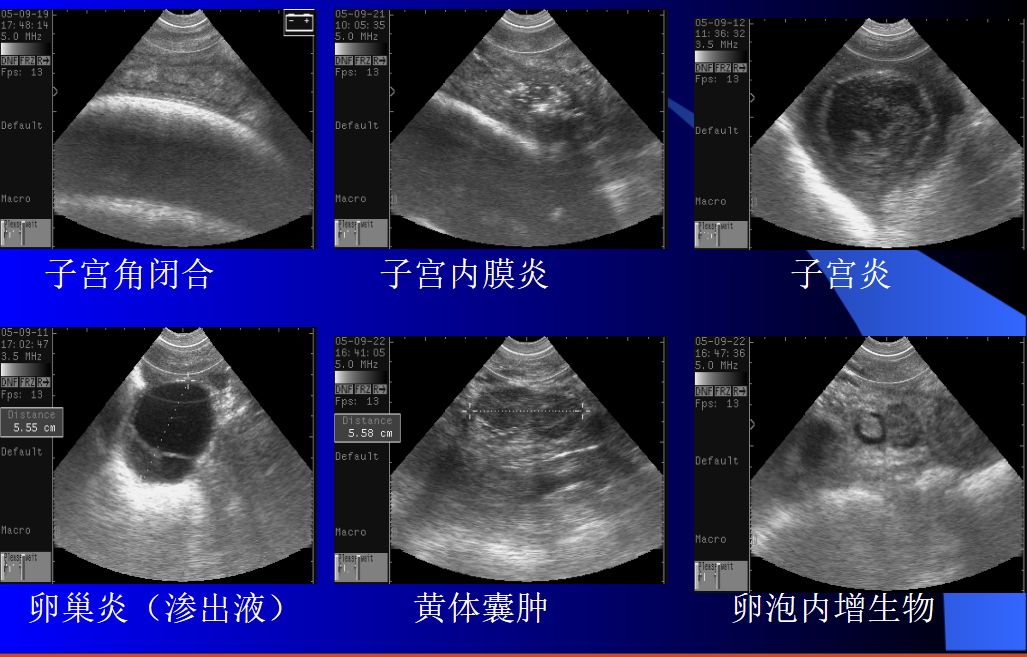

1、在操作过程中为避免操作失误,要先将直肠中的牛粪清除干净,牛粪会阻碍探头与直肠壁的耦合,影响操作效果;如果直肠中存在太多牛粪会造成牛努责,增加操作难度并加大应激。

2、在探头进入直肠前可先触碰一下子宫以了解其基本位置,节约操作时间,操作工程中要缓慢进行,避免因探头振动而造成牛努责。

3、另外还要区分胎囊、卵泡和膀胱,由于三者位置相近,并都呈无回声暗区,易造成判断失误;

4、探查部位应选择靠近生殖器官的部位,避免因胎囊沉于子宫角底部而造成失误。